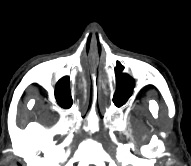

Околоносовые пазухи носа (синусы) представляют собой воздухоносные полости в костях лицевого и мозгового черепа, расположенные в непосредственной близости к полости носа. К околоносовым пазухам относят гайморовы пазухи (расположены в верхних челюстях), фронтальные синусы (в лобных костях черепа), клиновидная пазуха и ячейки решетчатого лабиринта.

Полости синусов изнутри выстланы слизистой оболочкой, они сообщаются с полостью носа, участвуют в очищении и согревании вдыхаемого воздуха и влияют на особенности тембра голоса. Околоносовые пазухи наиболее часто подвержены развитию острых и хронических воспалений, а также возникновению опухолевых образований, травматических повреждений и аномалий развития.

Золотым стандартом в диагностике патологических процессов пазух носа является мультиспиральная компьютерная томография. Это быстрый безболезненный и неинвазивный (то есть без вмешательства в организм) способ исследования состояния синусов. Метод основан на проникающей способности ионизирующего излучения и получения изображений органов и тканей организма за счет разной степени поглощения ими рентгеновских лучей.

Рентгеновские лучи лучше всего поглощаются костной тканью, поэтому кости хорошо видны на снимках КТ. Чтобы улучшить визуализацию мягких тканей и особенно патологических образований (в том числе полипов или опухолей), применяется внутривенное болюсное контрастирование. Для этого пациенту в вену вводится йодсодержащее контрастное вещество, которое улучшает видимость патологического очага на фоне здоровых тканей. С помощью методики контрастирования удается выявлять опухоли минимальных размеров, что повышает шансы пациента на успешное лечение и выздоровление.

Мультиспиральная компьютерная томография дает информацию о состоянии полости носа, носовой перегородки, степени воздушности околоносовых пазух, путей дренирования синусов, состоянии слезных каналов. Сканирование позволяет оценить толщину слизистой, наличие патологического содержимого в просвете пазух (уровня «жидкости»), выявить опухолевые образования. С помощью КТ можно провести точную диагностику травматических повреждений костей лицевого черепа, определить локализацию инородных тел, попавших в полости синусов.